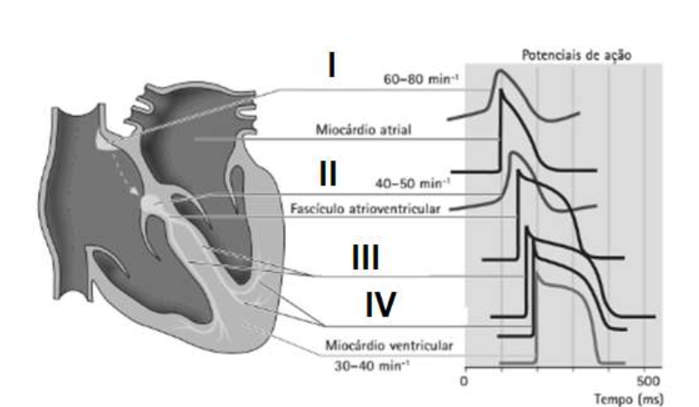

Células musculares cardíacas especializadas são responsáveis pela transmissão da excitação entre as células musculares cardíacas. Elas também contêm vários centros de marca-passos autônomos, que em condições fisiológicas podem ser controlados hierarquicamente. Observe a figura.

Fonte: Maurer, Martin H. Fisiologia Humana Ilustrada (2nd edição). Editora Manole, 2014.

Assinale a alternativa que correlacione os marcapassos do coração com os números I, II, III e IV, respectivamente.